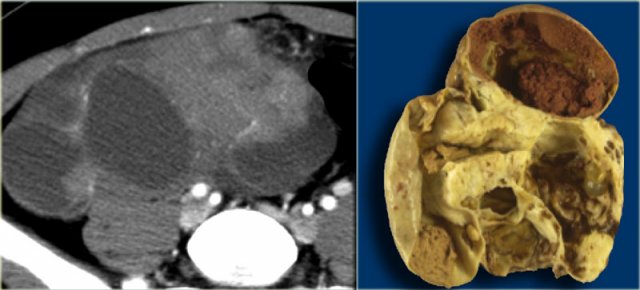

Ultrasound shows a very large multi-loculated cystic lesion in the region of the right adnex.

Some locules are anechoic. Others contain uniform low-level echoes, consistent with proteineous content, such as hemorrhage or, in this case, mucin. The septations are thin, except for the dorsal septations that appear somewhat thicker, partially caused by the lower scanresolution at great depth. The septations are avascular. There are no solid components. There was no ascites.

Despite the absence of solid components and despite the absence of vascularity on color Doppler, the size and the multi-loculated aspect of this lesion are suspicious for a cystic neoplasm and warant further evaluation.

The CECT shows similar findings. The locules are of different attenuation, consistent with varying protein content.

There is no ascites orperitoneal deposits and no lymphadenopathy.

At pathology this was a mucinous cystadenocarcinoma of low malignant potential.

Specimen of the mucinous cystadenocarcinoma Specimen of the mucinous cystadenocarcinoma

The thin, relatively avascular septae, the absence of frank solid components, the absence of ascites and peritoneal carcinomatosis and the absence of invasion, suggest a lesion of low malignant potential (LMP).

Note however, that this diagnosis can not be made on imaging findings alone.

Especially the absence of invasion in ovarian stroma cannot be judged reliably on imaging.